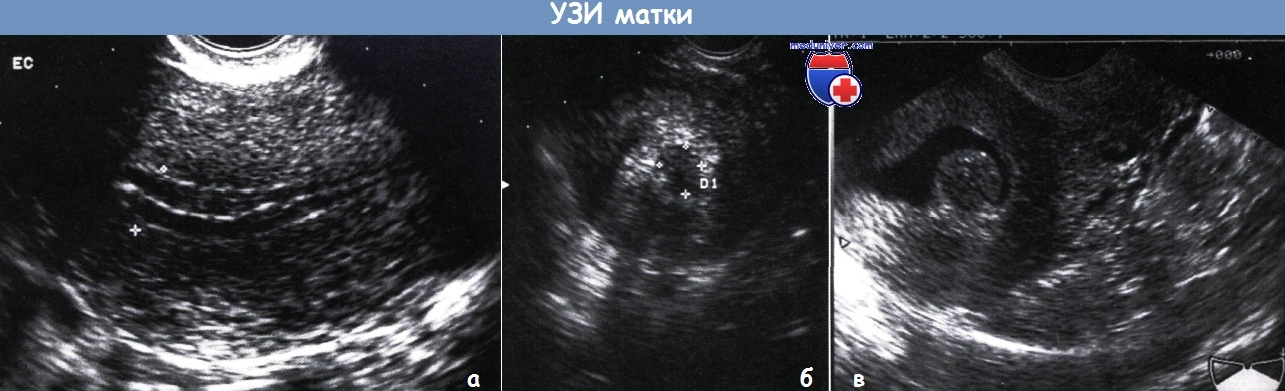

Ультразвуковое исследование (УЗИ) является наиболее распространенным и доступным методом для оценки толщины эндометрия. Вагинальное УЗИ позволяет получить более четкие изображения и измерить толщину эндометрия в различных фазах менструального цикла. Обычно измерения проводятся в срединной части эндометрия, и нормальные значения варьируются в зависимости от фазы цикла: в фолликулярной фазе толщина составляет 2-4 мм, в овуляторной – 6-8 мм, а в лютеиновой – 8-14 мм.